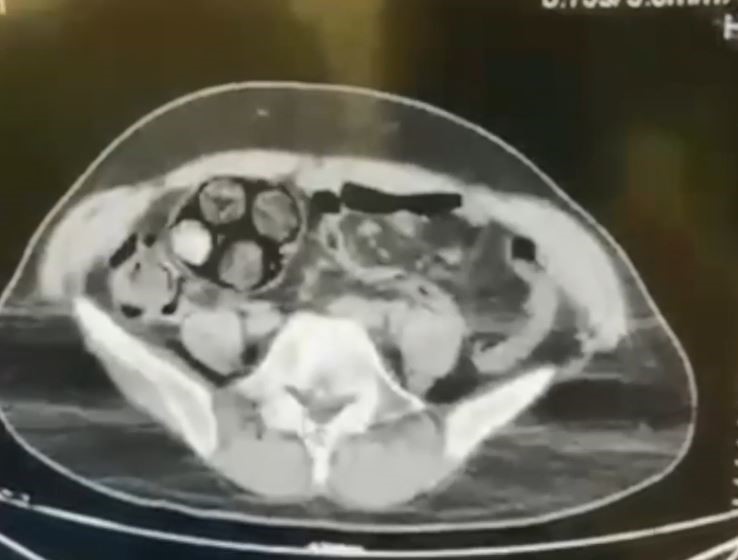

Edinilen bilgiye göre, Artvin İl Jandarma KOM Şube Müdürlüğü ekipleri, İran uyruklu Farshid Rafıeıeınsheykh (43) adlı şüphelinin 8 Mart tarihinde vücudu içerisine uyuşturucu madde gizleyerek Artvin’e getireceği bilgisi üzerine çalışma başlattı. Yapılan takip sonucu Artvin merkez Çayağzı Mahallesi’nde yakalanan şüphelinin üst aramasında herhangi bir suç unsuruna rastlanmadı. Bunun üzerine şüpheli, Ceza Muhakemesi Kanunu’nun 75. maddesi gereği iç ve dış beden muayenesi için Artvin Devlet Hastanesine sevk edildi. Çekilen tomografi sonucu zanlının bağırsaklarında 10 paket tespit edildi. Cerrahi müdahale ile çıkarılan paketlerin içinde toplamda 350 gram metamfetamin maddesi olduğu belirlendi. Gözaltına alınan İranlı zanlı hastanede müşahede altına alınırken, olayla ilgili soruşturma başlatıldı.